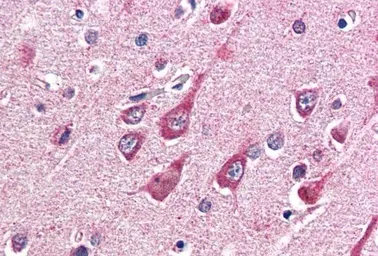

IHC-P analysis of human cortex using GTX89131 O-GlcNAc transferase antibody, Internal.

Antigen retrieval : citrate buffer pH 6

Dilution : 5μg/ml